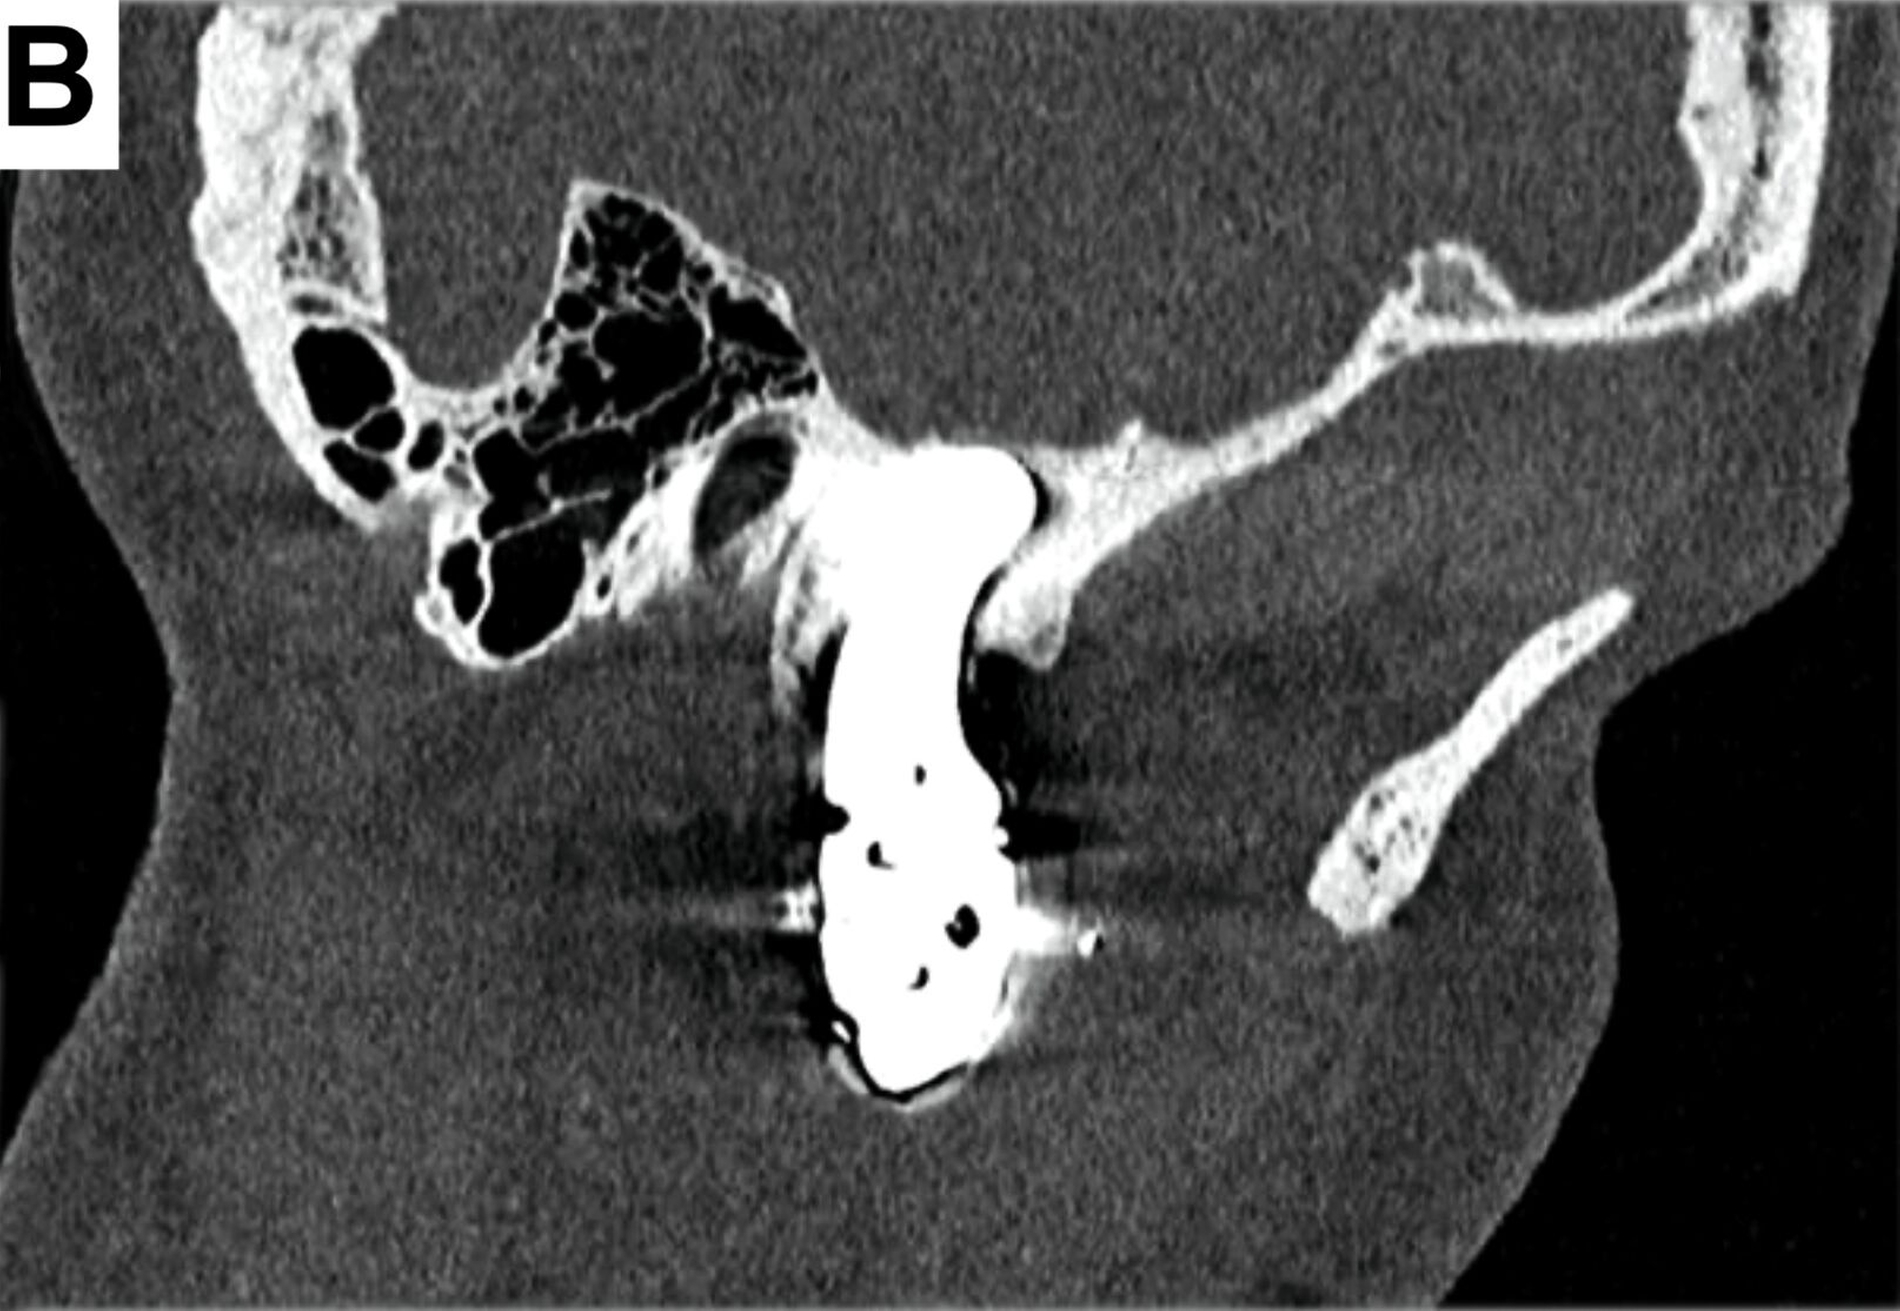

Bei der computertomografischen Untersuchung, die während der Patientenvorstellung durchgeführt wurde, wurde der totale Ersatz des rechten Kondylus durch die bereits beschriebene Endoprothese festgestellt, jedoch ohne Ersatz der Fossa mandibulae, was einem partiellen Kiefergelenkersatz entsprach. Das in situ befindliche Prothesenwerkstück hatte bereits zu einer nahezu vollständigen Erosion der mittleren Schädelbasis geführt (Abbildung 1).

Um eine weitere Dislokation nach intrakraniell zu vermeiden, erfolgte eine Woche nach der Erstvorstellung der Patientin die Entfernung des Endoprothesenwerkstücks (Abbildung 2).